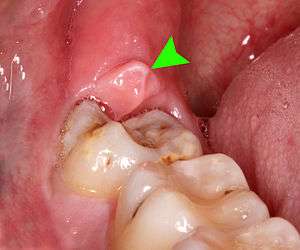

| Pericoronitis associated with the lower right third molar (wisdom tooth). | |